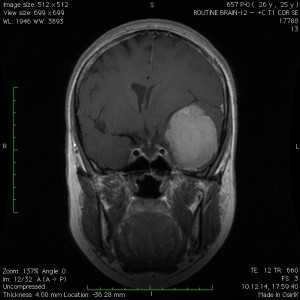

Пациентка В., 25 лет. В возрасте 9 лет перенесла острый лимфобластный лейкоз, по поводу чего проводилась лучевая терапия.

За 2 месяца до поступления в стационар появилась боль в левой височной области, левом глазном яблоке, слезотечение. Консультирована офтальмологом — выявлено высотные левого глазного яблока на 6 мм, по сравнению с правом глазным яблоком, а также признаки внутричерепной гипертензии в виде застойных дисков зрительных нервов. При МРТ выявлена больших размером внемозговая опухоль средней черепной ямки с гиперостозом и распространением в глазницу слева.

Выполнена операция — удаление менингиомы крыльев клиновидной кости с резекцией гиперостоза и использоваием интраоперационной метаболической навигации (ультрафиолетовая флюоресцентная микроскопия)